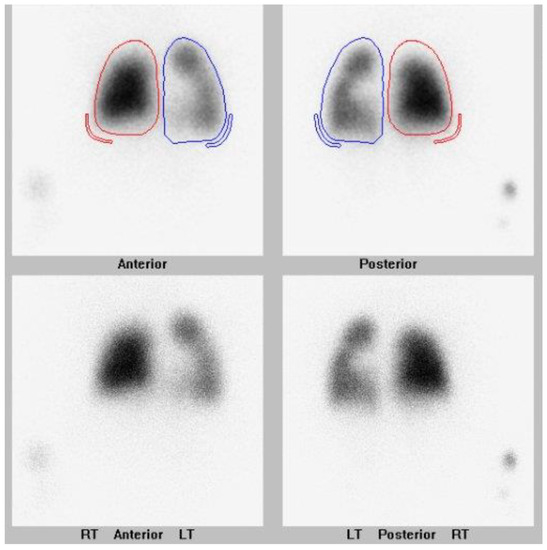

This case study is an example of a child with a history of prematurity who presented multivessel PVS along with a shunt lesion. They are being treated with multimodal management, including surgical and catheter-based interventions and targeted inhibition of myofibroblast proliferation with imatinib. They are now an active toddler weaned off oxygen and continue on gastrostomy tube supplemental feeds. They have had nine cardiac catheterizations and two cardiac surgeries to intervene on pulmonary veins. They continue to be monitored closely with echocardiograms and lung scans as indicated. Their lung scan post catheterization #9 is shown in Figure 2. They have overall tolerated imatinib, but their growth has been slow.

Figure 2. Most recent nuclear lung perfusion scan of patient who is now 3 years old with multivessel pulmonary vein stenosis involving all pulmonary veins. Patient has undergone 2 cardiac surgeries and 9 cardiac catheterizations on her pulmonary veins. Differential pulmonary perfusion as quantitated based on Tc-99m MAA localization is 34% left lung and 66% right lung. There is further diminished perfusion in the left compared to the right lung. Within the right lung, there is a similar pattern of diminished perfusion in the apex relative to the remainder of the lung. Within the left lung, there is interval slightly improved relative perfusion in the upper lung, and relatively diminished perfusion in the lower lung. Right lung is outlined in red. Left lung is outlined in blue.